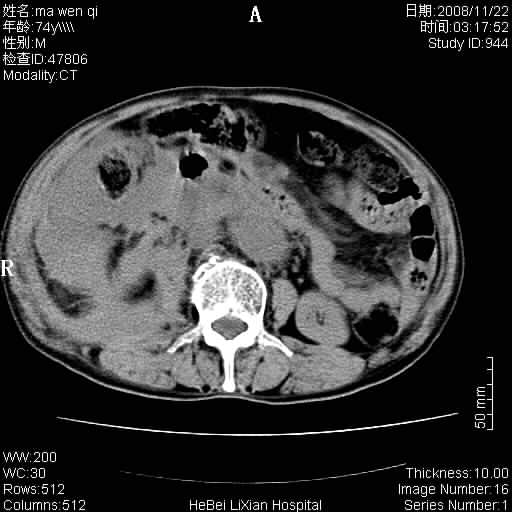

患者男 74岁.突然昏迷,休克6小时.血压70/30,头颅ct未见异常,既往体健.

补充病史,保留导尿10小时,尿袋内只有少许尿液,患者于住院后15小时后去世.

腹主动脉、双侧髂动脉夹层动脉瘤破裂出血进入腹腔。

1)考虑双侧髂动脉瘤并右侧动脉瘤破裂出血,右侧腹膜后及腹腔积血。2)双侧腹股沟疝。

1)考虑,腹主动脉、双侧髂动脉夹层动脉瘤破裂伴右侧腹膜后及腹腔积血。2)双侧腹股沟疝。

1)考虑胸、腹主动脉、双侧髂动脉瘤并右侧动脉瘤破裂出血,右侧腹膜后及腹腔积血。2)双侧腹股沟疝。